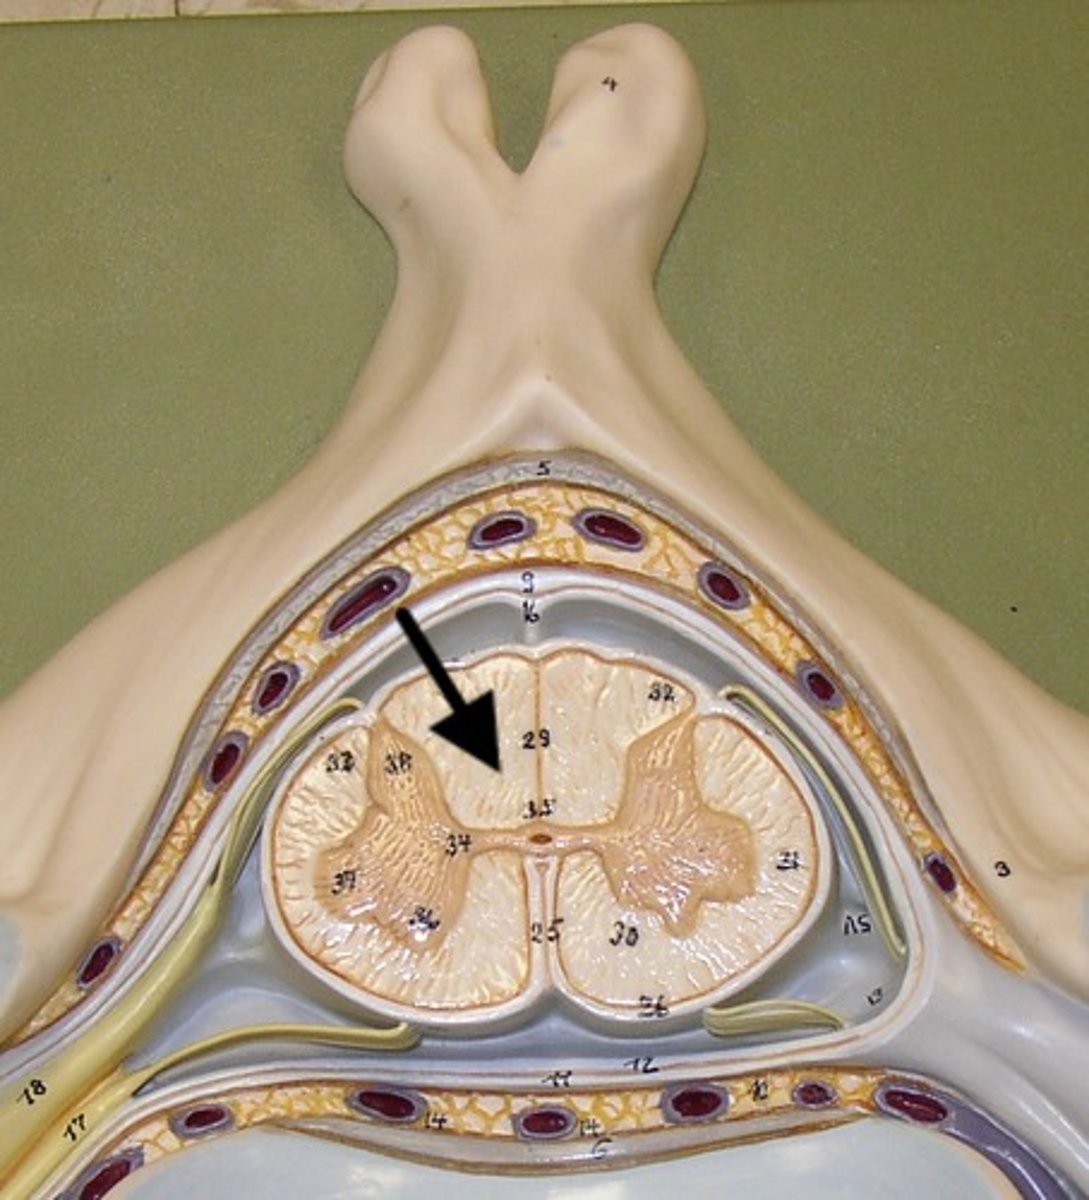

Gray Matter

1

Posterior Horn

2

Anterior Horn

3

Lateral Horn

4

Gray Commissure

6

Central Canal

5

White Matter

7

Posterior funiculus

8

Anterior Funiculus

9

Lateral Funiculus

10

Dura mater

arachnoid mater

pia mater

epidural space

subdural space

subarachnoid space